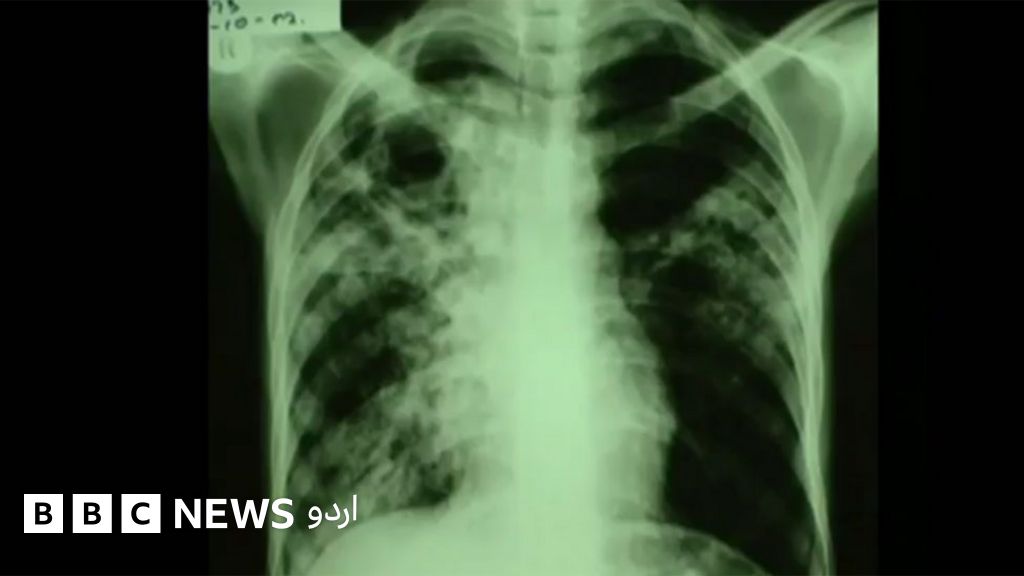

تپِ دق کی تشخیص میں اہم پیش رفت

اوکسفرڈ اور برمنگھم کے سائنس دانوں نے کہا ہے کہ انھوں نے تپِ دق کی تشخیص میں جینوم سیکونسنگ کا طریقہ استعمال کر کے اہم پیش رفت حاصل کر لی ہے۔

اس کا مطلب یہ ہے کہ اس سے پہلے جن مریضوں کو درست دوا کے انتخاب کے لیے مہینوں انتظار کرنا پڑتا تھا اب ان کے اندر بیماری پیدا کرنے والے جراثیم کی شناخت چند دنوں کے اندر اندر ہو سکے گی، جس سے علاج مزید موثر ہو جائے گا۔